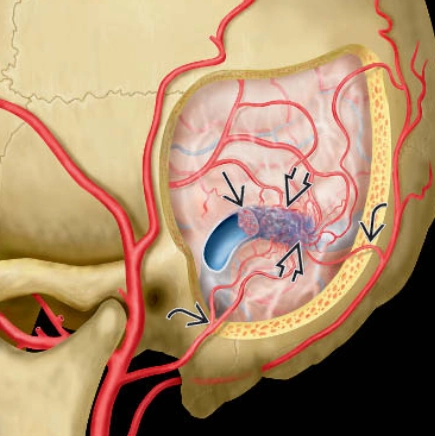

• Rò động-tĩnh mạch màng cứng (Dural Arteriovenous Fistula - DAVF)

• Dò động-tĩnh mạch màng mềm (Pial Arteriovenous Fistula - pAVF)